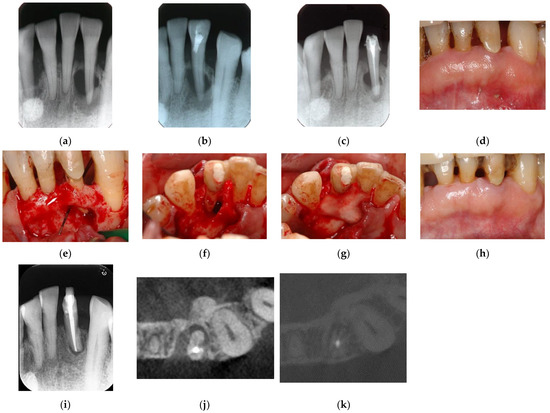

Persistent periapical lesions may ultimately require endodontic surgery, such as apicoectomy and intentional replantation (Figure 6) [49]. Although this type of lesion is in the endodontic domain and is caused by iatrogenic errors, proper and successful treatment requires not only endodontic surgery but also concurrent guided tissue regeneration (GTR) [16,50].

Figure 6. Clinical case 5. Female, age 36 yrs. (a) Intraoral view of the upper left first maxilla at baseline, showing two sinus tracts (arrows). (b) Preoperative periapical radiograph, in which the “bone” defect appeared as a radiolucent area around the MB root. (c) Periapical radiograph after root canal retreatment. (d) View after flap retraction and debriding of the defect, showing two bone defects. (e) GTR treatment with two resorbable membranes. (f) Periapical radiograph after regenerative treatment. (g,h) Preoperative CBCT showing a radiolucent lesion on the periapical and bifurcation areas. (i,j) CBCT findings after endodontic retreatment. (k,l) Follow-up CBCT 10 years after treatment, showing healing of the two bone defects.

Despite the many classifications and treatment modalities of EPLs, treatment of these combined endodontic and non-endodontic problems remains challenging, with outcomes differing among different dentists. Endodontic retreatment is associated with a relatively high failure rate, indicating the need for surgical treatment combined with both endodontic and periodontal regenerative treatment of teeth that are beyond treatment (Figure 6 and Figure 7). That is, treatment outcomes depend on the status of the affected teeth diagnosed with EPLs.